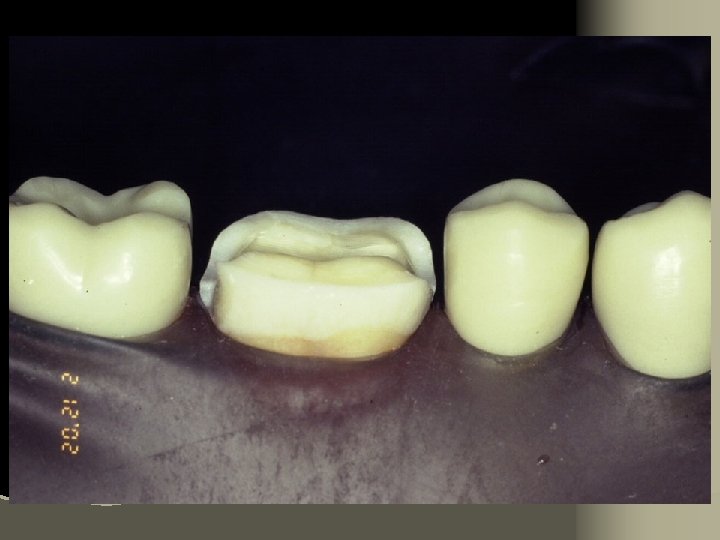

HF etch Intaglio surfaces only

Cementation Procedure 1. Remove temporary and all residue of temporary cement 2. Check occlusion on adjacent teeth (mylar shimstock and articulating paper) 3. Place rubber dam 4. Clean tooth with pumice and rubber cup, rinse and lightly dry 5. Try in restoration for fit.

6. Adjust proximal contacts if necessary 7. Evaluate shade intraorally using water soluble try-in paste (optional) 8. Rinse out try-in paste and air dry 9. Etch inside of restoration (HF porcelain etchant X 2 minutes), rinse with distilled water and air dry 10. Place drop of silane (porcelain primer) on intaglio surface for 1 minute, lightly air thin to evaporate solvent